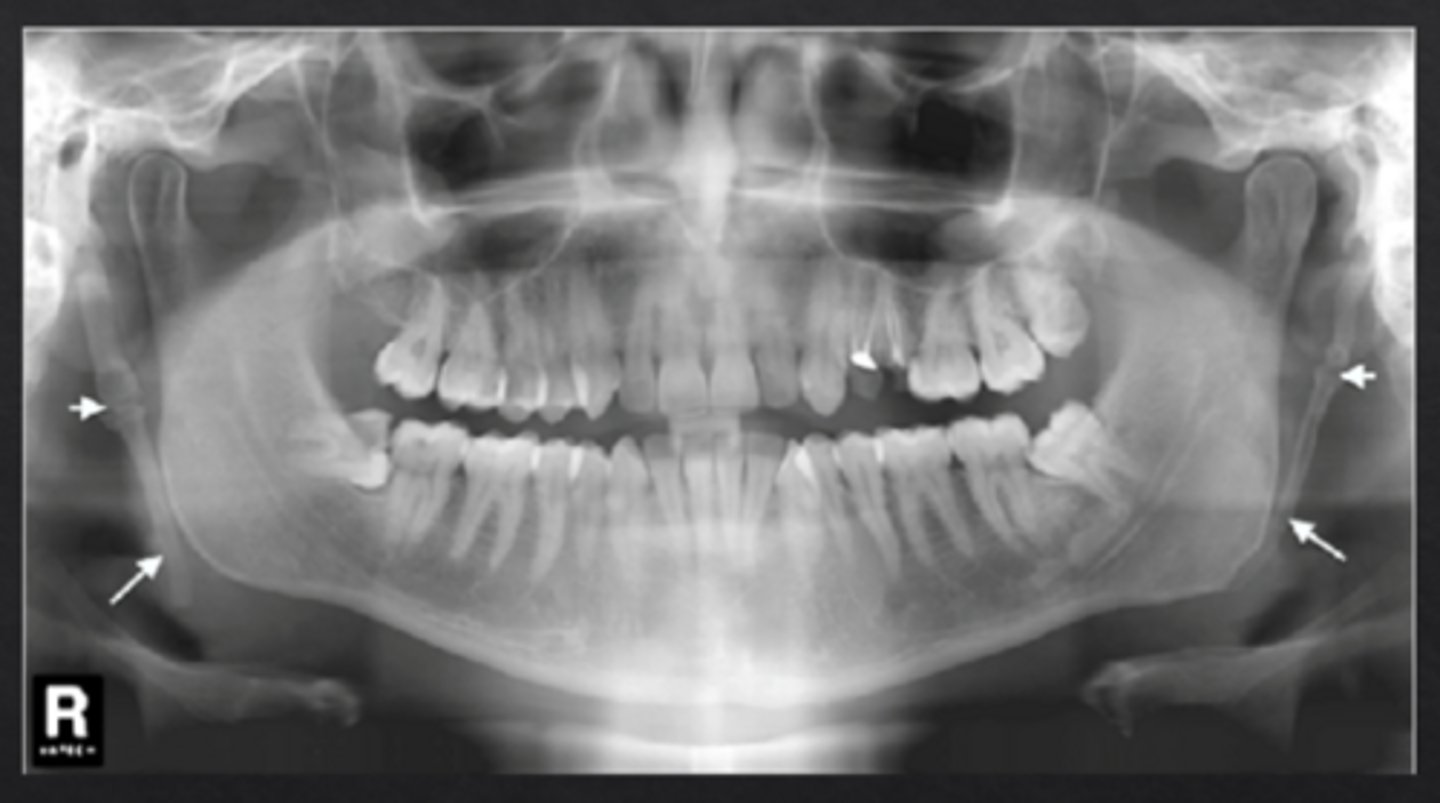

What is osteoporosis?

Systemic skeletal disease characterized by low bone mineral density and deterioration of bone microarchitecture

What radiographic changes are associated with osteoporosis?

Loss of trabecular architecture and thinning of mandibular cortical bone

What is idiopathic osteosclerosis?

"Dense bone island" an area where normal trabecular bone is replaced with dense cortical bone

How does idiopathic osteosclerosis appear radiographically?

Region of dense radiopaque bone, blends with surrounding bone